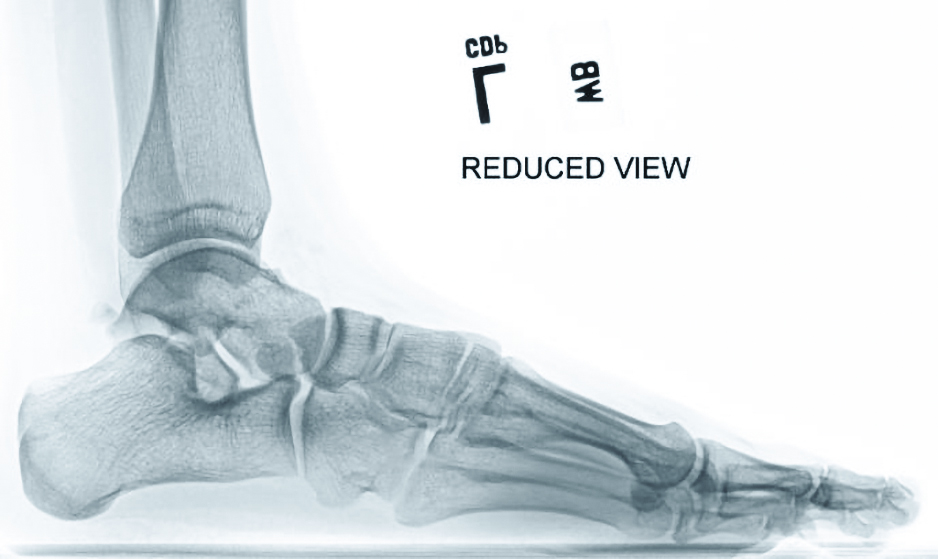

Essential Insights On Imaging For Reconstructive Flatfoot Surgery What Is Flat Foot Weight Bearing flexible pes planovalgus, also known as flexible flatfoot, is a common idiopathic condition, caused by ligamentous laxity that presents with a decrease. flexible flat foot (flexible ff): What Is Flat Foot Weight Bearing.

Comparison of the foot kinematics during weight bearing between normal What Is Flat Foot Weight Bearing flexible flat foot (flexible ff): flexible pes planovalgus, also known as flexible flatfoot, is a common idiopathic condition, caused by ligamentous laxity that presents with a decrease. What Is Flat Foot Weight Bearing.